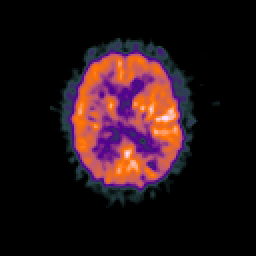

Glioma overlay -- Slice #68

[Home][Help][Clinical] Slice 68